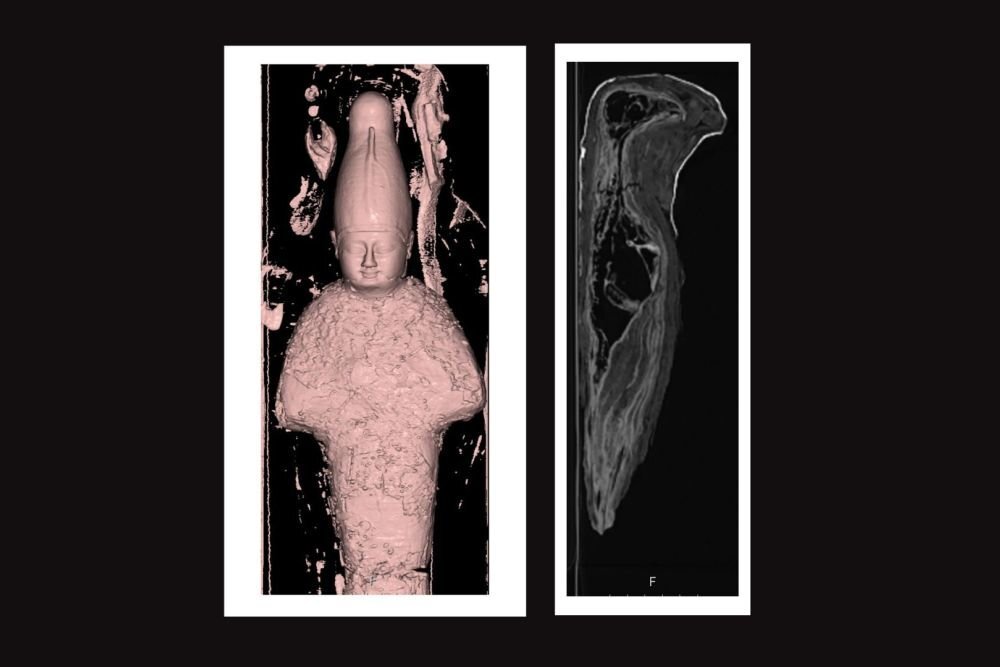

Теперь же египтологи призвали на помощь радиологов во главе с Марсией Джавитт, профессором Университета имени Джорджа Вашингтона. Сканирование показало, что одна из мумий представляет собой "сверток", плотно набитый зерном и землей. Другая же хранит останки птицы, возможно, сокола, у которого отсутствует левая лапа и несколько органов. Причем ученые не знают, почему.

"Зерновая" мумия является антропоморфной, то есть она выполнена в виде человека. Ее длина составляет около 45 сантиметров. Ученые считают, что она была посвящена культу Осириса - не только царя загробного мира, но и бога жизни и возрождения.

Словом, это была не настоящая мумия, а ритуальный артефакт. Он символизировал связь Осириса с жизнью, смертью и плодородием почвы. Вторая исследованная мумия, вероятно, тоже была тесно связана с мифологией. Ее длина составляет 25 сантиметров. Она была изготовлена в форме птицы.

Для изучения этой мумии радиологи применили комбинированный метод компьютерной томографии, варьируя мощность рентгеновского излучения. Это позволило определить, что шея у птицы, вид которой пока достоверно определить не удалось, была сломана, но сделано это было уже после ее смерти.

Сканирование также показало, что у птицы были удалены некоторые органы, но не все. К примеру, сердце осталось. Потребуются дополнительные исследования, чтобы определить, каких именно органов не хватает. Кроме того, музей планирует провести радиоуглеродное датирование. Это поможет впервые точно определить возраст данных артефактов.